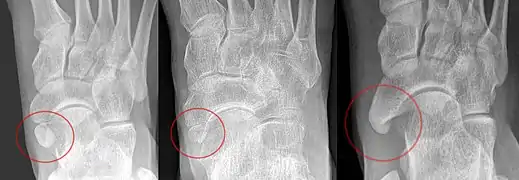

Accessory navicular types, from left to right: Type 1, 2 and 3.

An accessory navicular bone, also called os tibiale externum, occasionally develops in front of the ankle towards the inside of the foot. This bone may be present in approximately 2–21% of the general population and is usually asymptomatic.[18][19][20] When it is symptomatic, surgery may be necessary.

The Geist classification divides the accessory navicular bones into three types.[20]

• Type 1: An os tibiale externum is a 2–3 mm sesamoid bone in the distal posterior tibialis tendon. Usually asymptomatic.

• Type 2: Triangular or heart-shaped ossicle measuring up to 12 mm, which represents a secondary ossification center connected to the navicular tuberosity by a 1–2 mm layer of fibrocartilage or hyaline cartilage. Portions of the posterior tibialis tendon sometimes insert onto the accessory ossicle, which can cause dysfunction, and therefore, symptoms.

• Type 3: A cornuate navicular bone represents an enlarged navicular tuberosity, which may represent a fused Type 2 accessory bone. Occasionally symptomatic due to bunion formation.